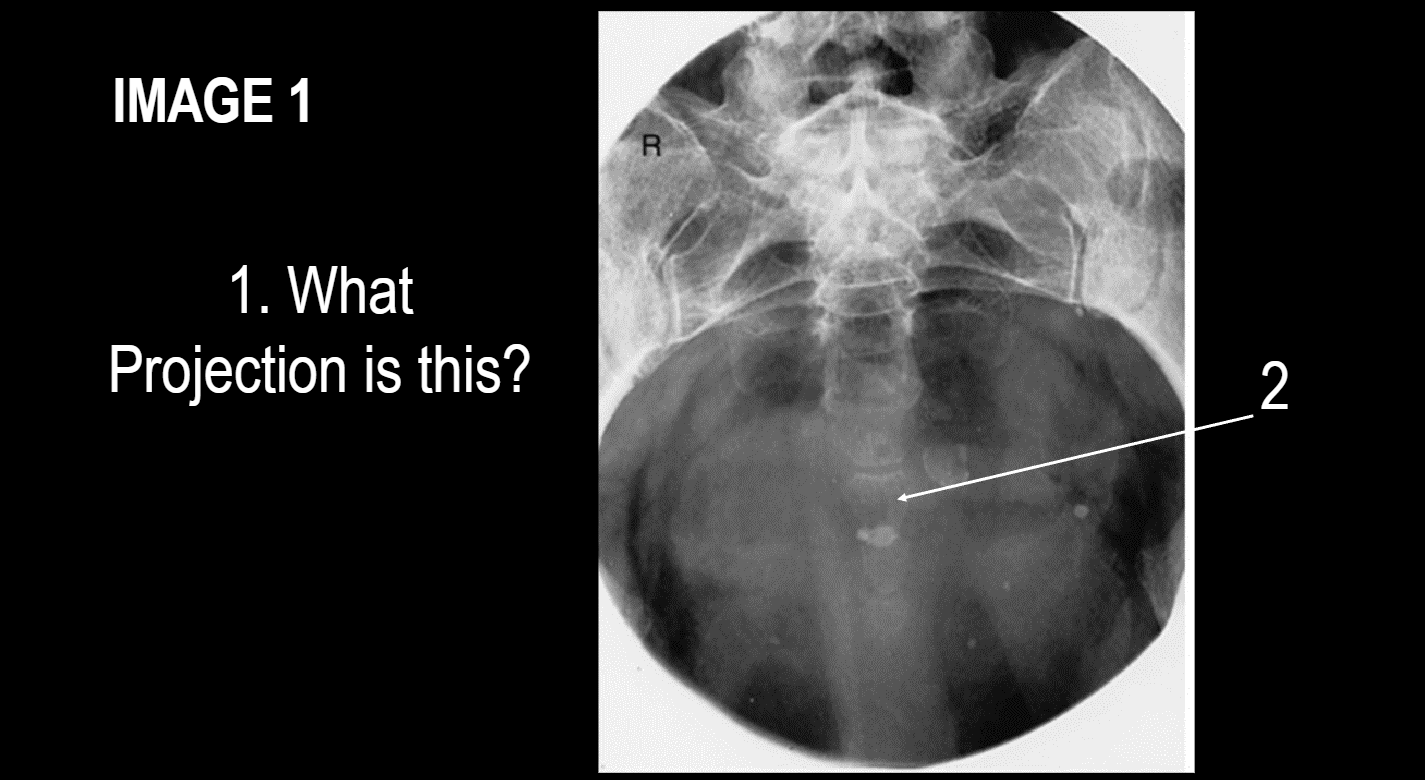

Projection?

Ap oblique modified cleaves

Projection ?

AP OBlique modeified cleaves

2

coccyx

3

apex of sacrum